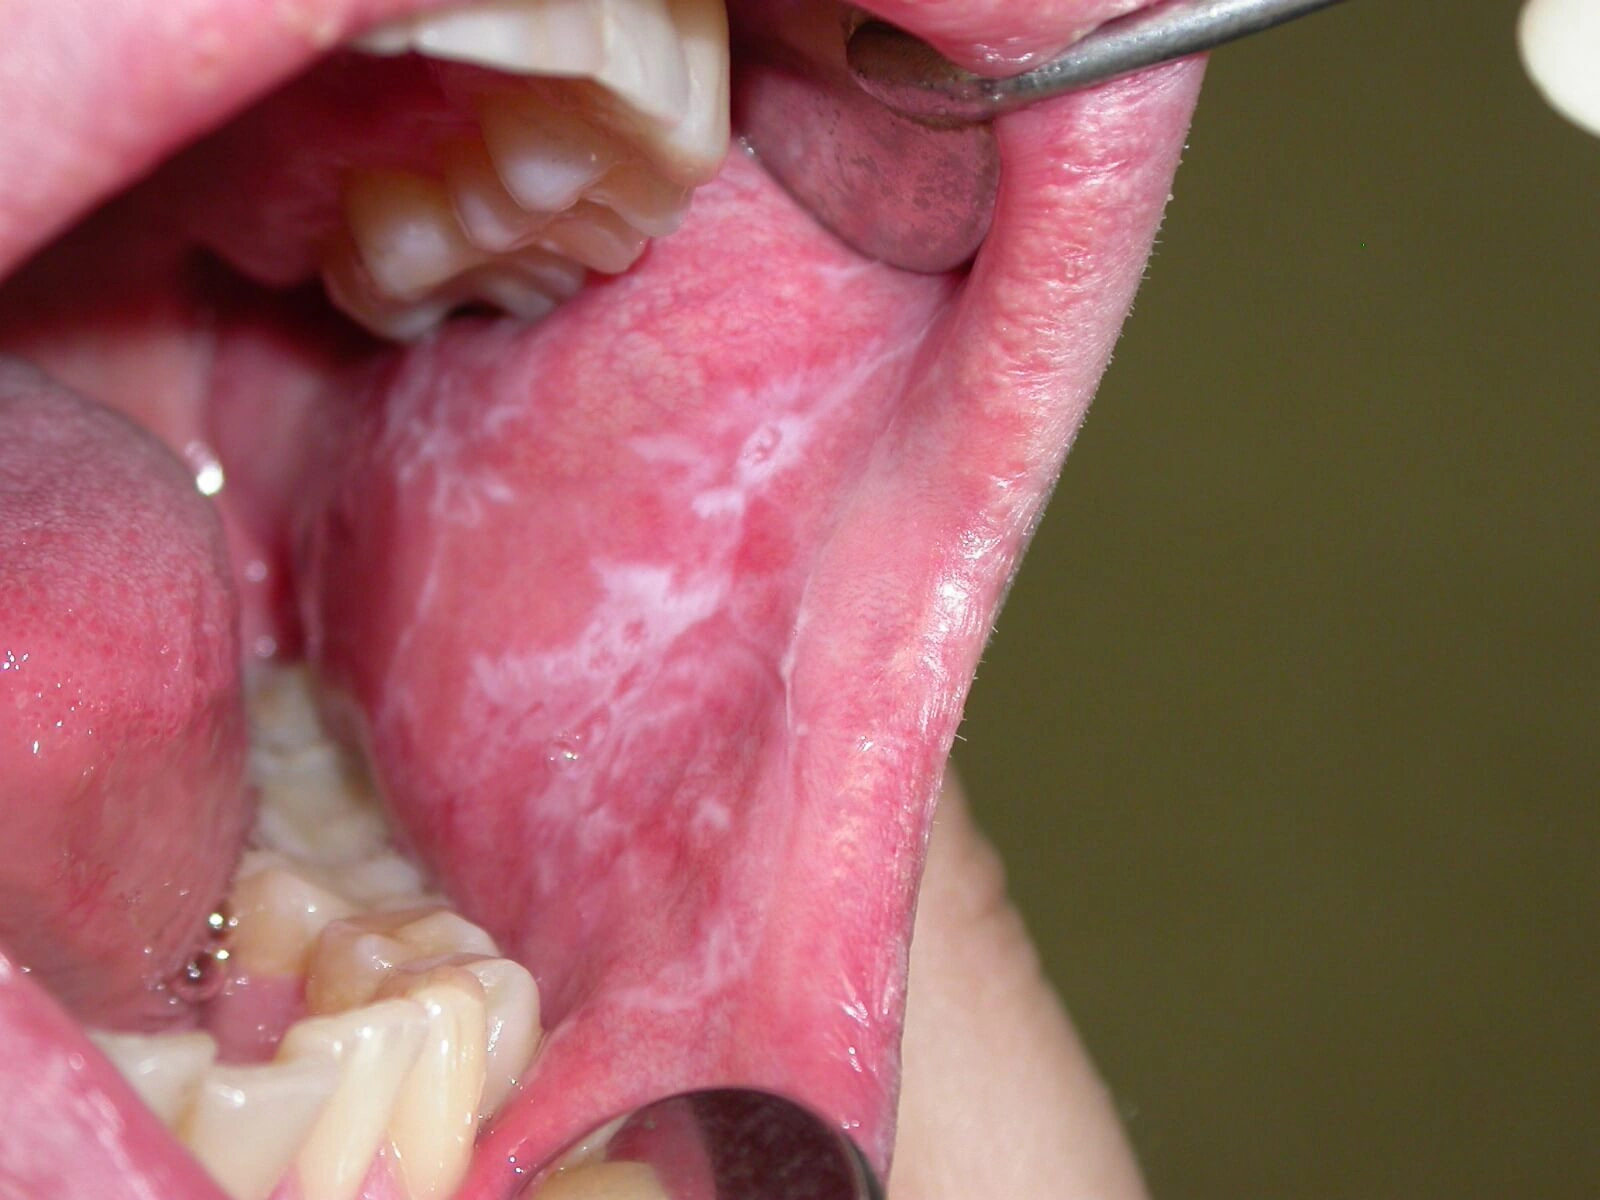

Ağız leykoplakiyası yanaqların və dodaqların daxili səthində, dildə, diş ətində və damaqda keratinləşmiş epiteldən (dərinin üst təbəqəsi) ibarət ağ qalınlaşmaların əmələ gəldiyi xəstəlikdir. Daimi travmaya görə canlı epitel hüceyrələri sıx buynuz pulcuqlara çevrilir. Vaxt keçdikcə bu cür tərəzilər lövhələr əmələ gətirir, onlar tədricən daha qabalaşır və sərtləşirlər. Eyni zamanda, keratinləşdirilmiş epitel hüceyrələri bədxassəli degenerasiyaya meyllidir - statistikaya görə, leykoplakiya olan insanların təxminən 17% -i ağız boşluğunun skuamöz hüceyrəli karsinomasını inkişaf etdirir.